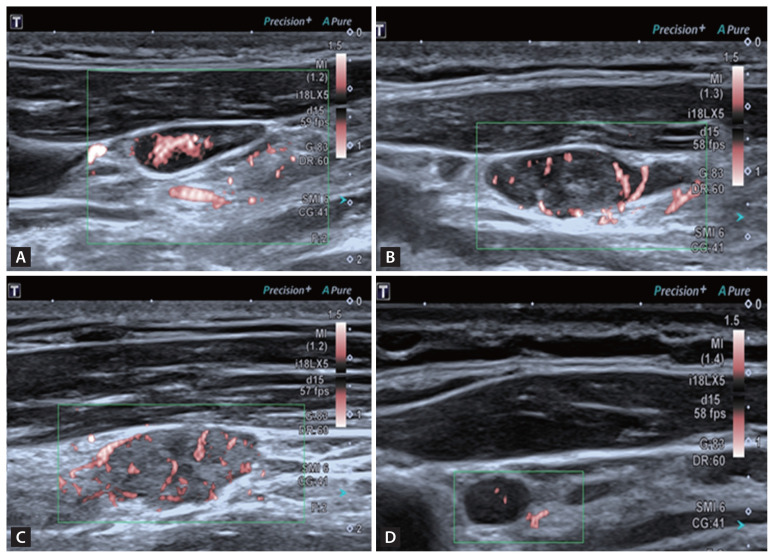

背景/目的:本研究旨在利用多模态超声参数建立一个诊断模型,以帮助检测甲状腺乳头状癌(PTC)患者的颈淋巴结转移:研究对象包括 69 名 PTC 患者的 84 个可疑淋巴结,所有患者均接受了细针穿刺,并获得了病理结果。研究分析了传统灰阶超声、剪切波弹性成像(SWE)和超微血管成像的数据。通过比较良性组和转移组的主要超声特征,利用费雪逐步判别分析建立了一个诊断模型。通过自我测试、交叉验证和接收器操作特征曲线分析评估了模型的有效性:淋巴结(X1)、皮质高回声(X2)、血管形态(X4)和 SWEmean(X7)这四个特征是判别分析中不可或缺的部分,并得出以下等式:Y1 = -3.461 + 2.423x1 + 0.321x2 + 1.620x4 + 0.109x7,Y2 = -8.053 + 0.414x1 + 2.600x2 + 2.504x4 + 0.192x7。如果 Y1 < Y2,该淋巴结将被诊断为转移性淋巴结。该模型的曲线下面积为 0.833,灵敏度为 83.33%,特异度为 83.33%:通过费雪逐步判别分析建立的多模态超声诊断模型证明能有效识别 PTC 患者的转移性淋巴结。

Methods: The study included 84 suspicious lymph nodes from 69 PTC patients, all of whom underwent fine needle aspiration with pathological results. Data from conventional grayscale ultrasound, shear wave elastography (SWE), and superb microvascular imaging were analyzed. Key ultrasound features were compared between benign and metastatic groups to create a diagnostic model using Fisher's stepwise discriminant analysis. The model's effectiveness was assessed with self-testing, cross-validation, and receiver operating characteristic curve analysis.